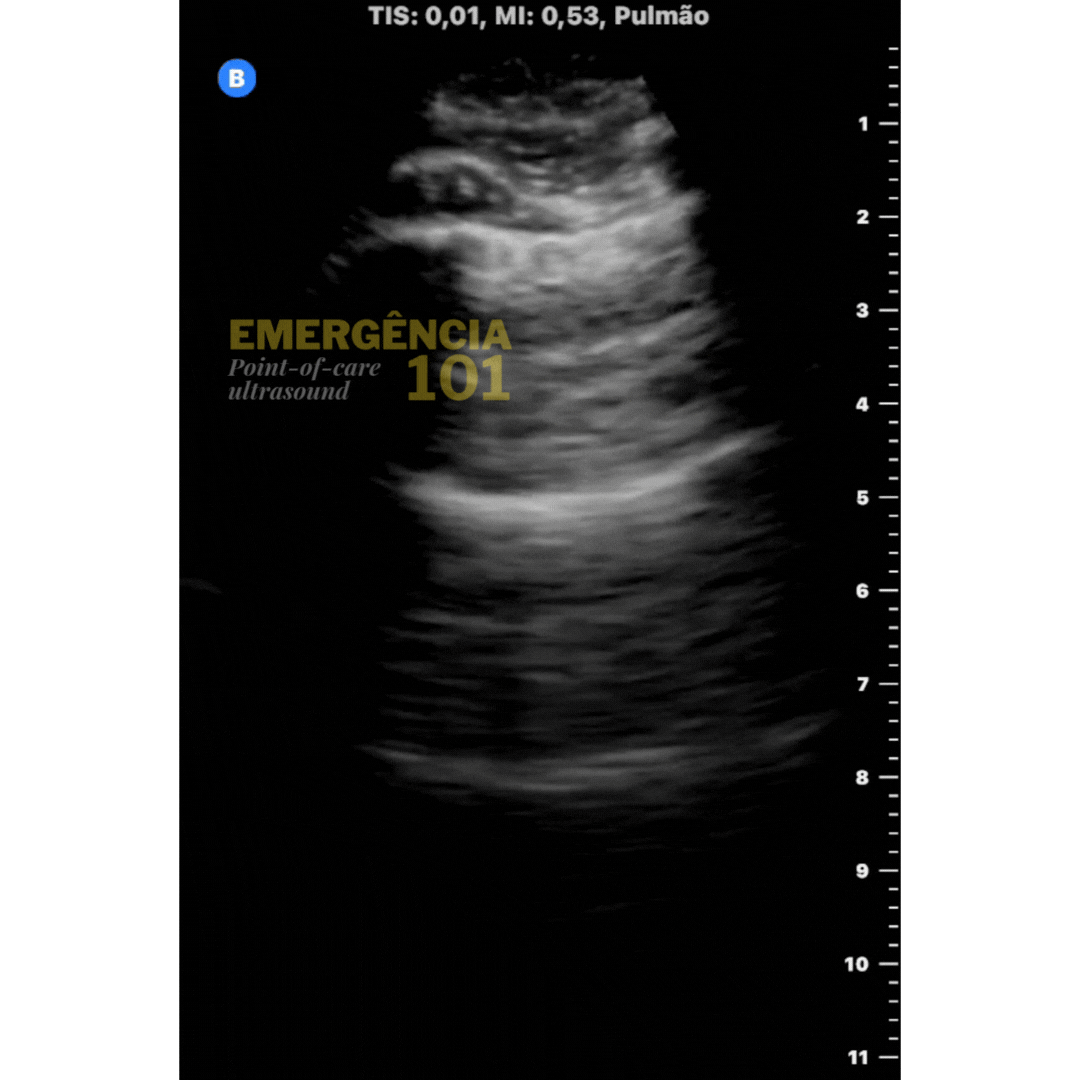

Figura 5a. Consolidação subpleural não-translobar em paciente com pneumonia. "Shred sign". Acervo pessoal do autor.

Figura 5c. Irregularidade pleural do "shred sign" para comparação com a tomografia (observação: pacientes diferentes). Acervo pessoal do autor.